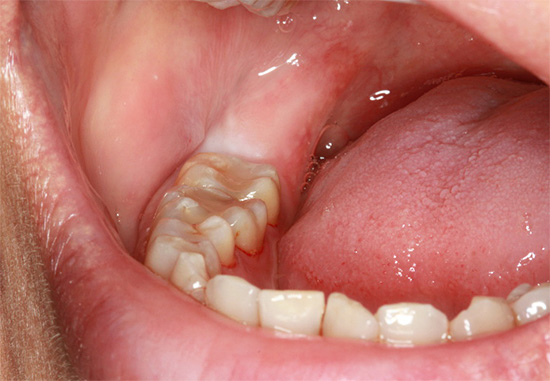

Deve-se prestar atenção especial a uma coluna na lista de preços, como a remoção de um dente retardado (não cortável) e meio dente (parcialmente aparecido). Normalmente, essa categoria reflete o problema comum que muitas pessoas enfrentam quando um dente do siso corta com apenas um ou dois tubérculos através da gengiva devido à falta de espaço ou está localizado sob a gengiva ou no osso.

Isso não traz muita preocupação para a maioria das pessoas, mas, em alguns casos, há situações clínicas em que o dente do siso repousa sobre o próximo sétimo dente, causando dor intensa à medida que o "empurra". A dor também pode ocorrer quando um dente do siso parcialmente aparecido é coberto com uma capa de gengiva, que supina constantemente e seriamente. Tudo isso e várias outras situações requerem intervenção cirúrgica imediata.

A natureza da complexidade da intervenção é determinada pelo cirurgião-dentista em uma instituição especializada e, como observado acima, a remoção nunca começa sem um raio-X. A complexidade de sua remoção depende da natureza da localização do dente no orifício. Se o dente estiver localizado completamente no osso e quase estiver ao longo da mandíbula, a operação poderá demorar muito tempo, à medida que as gengivas forem excisadas, o osso será cortado com a separação da coroa e das raízes dos dentes, seguido de uma extração em fases do orifício ósseo.